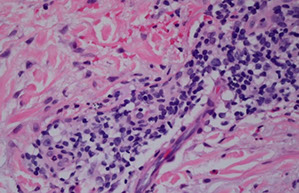

Leukocytoclastic vasculitis (LCV)

Pruritic and palpable, sometimes c livedo reticularis or stellate infarcts

- MCC are Strep and meds

- is a vasculitis of the post-capillary venules

- usually idiopathic, but sometimes can be caused by drugs, infx, chemicals, cancer or systemic dz

- on req, may hint at this dz c "palpable purpura", most diagnostic biopsy from fresh lesion (from 18-24 hrs old)

- if not in the skin, usually involves joints, GI and kidneys

Micro: neutros invade the perivascular region; vessel wall may be expanded, due to deposition of fibrin in fibrinoid vascular necrosis

- RBC extravasation

- karyorrhexis around vascular space looks like space dust; or dismembered ants and scattered ant heads (leukocytoclasis)

- eosinophils and sometimes fibrin thrombi can be seen

DIF: IgG, M or complement in granular pattern

Px: good if not systemic

Leukocytoclastic vasculitis